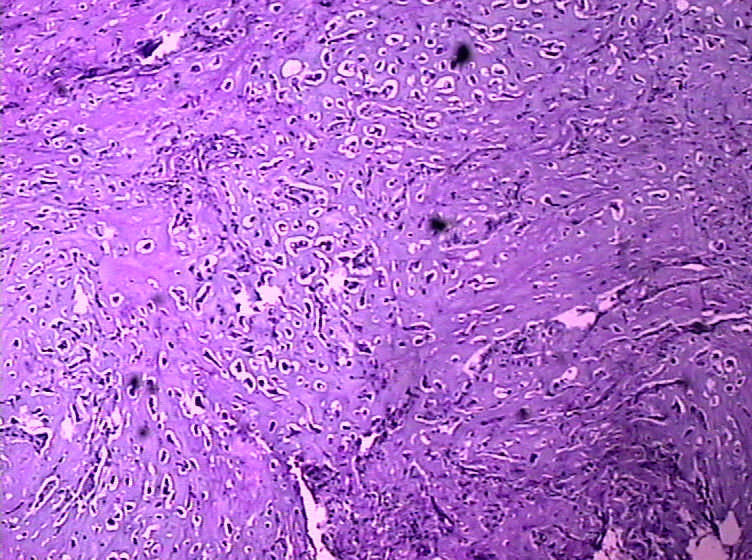

女,4岁,咽喉壁肿物。